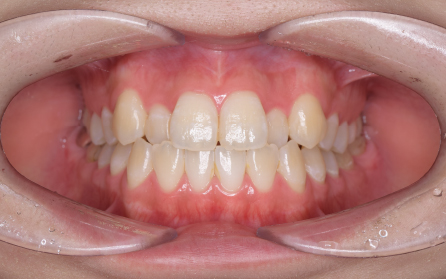

19歳 女性

主訴 「前歯のでこぼこを治したい」

診断 「両側側切歯のクロスバイトを伴う叢生症例」

上下前歯部の叢生の改善のため、歯と歯の間を0.5mm程度削ってスペースを確保しながら歯を並べました。患者さんの協力(マウスピースの使用状況等)も良好で、前歯が前方に突出することなく側切歯(2番目の歯)のクロスバイトも改善されました。前歯が突出しないように治療計画をたてないと口唇が閉じにくくなったり、口元がもっこりしてしまいます。治療期間は18か月でしたが、動的治療後は歯を安定させるために保定装置の使用が必要です(最低2年)。矯正治療では患者さんの協力が非常に重要であり(特にマウスピース矯正の場合は使用時間)、治療結果や治療期間に影響します。また、歯の移動にはワイヤー矯正、マウスピース矯正にかかわらず歯根吸収、歯肉退縮、歯髄壊死のリスクがあります。